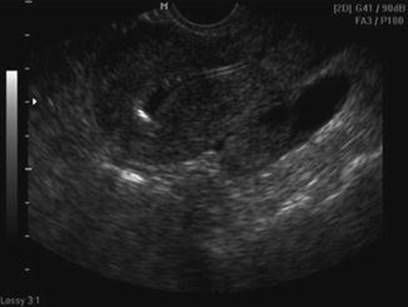

Fig. 2.13

Preovulatory follicle

Monitoring preovulatory follicles with follicle diameters (Fig. 2.13) has limitations to predict oocyte quality. Although the follicle growth pattern may be a predictive indicator of the oocyte quality [12], it is difficult to identify individual follicle changes in multiple ovarian follicle growth induced by gonadotropin stimulation.